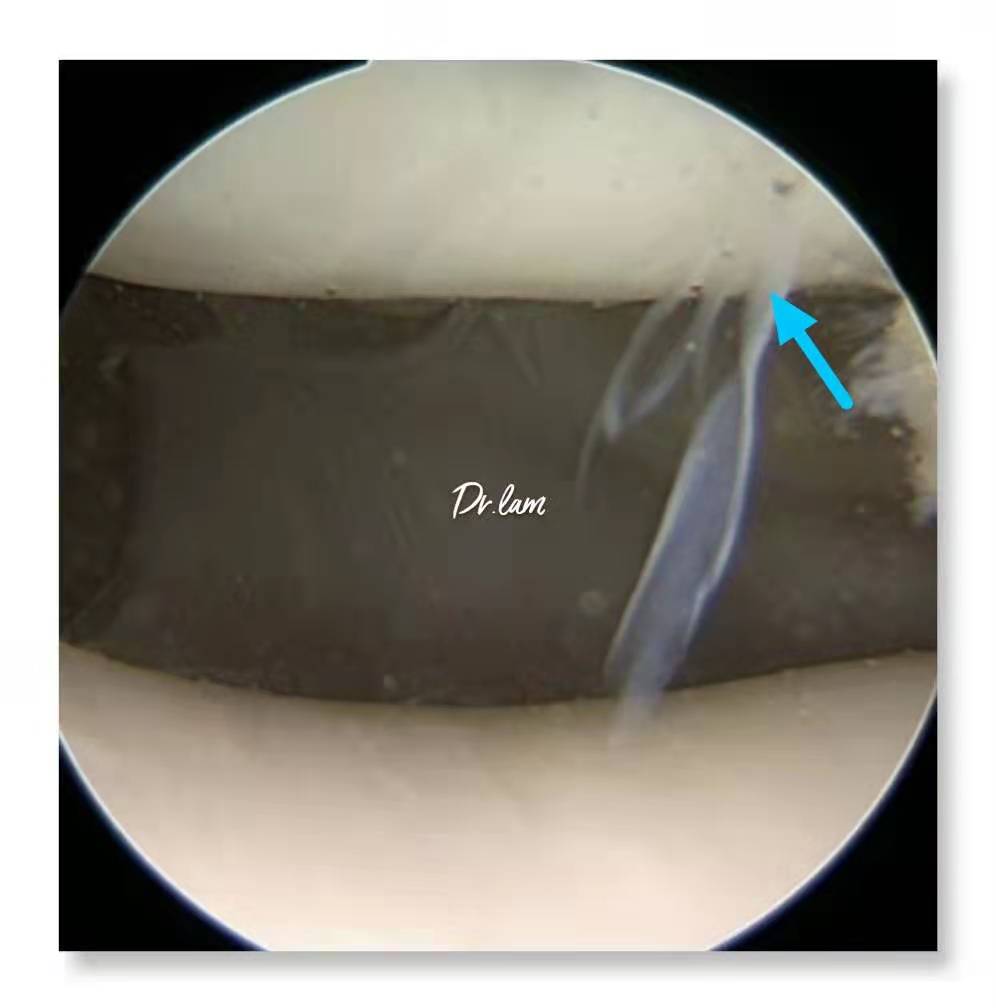

最后,我们再一起看看几张图片,加深了解这个容易被忽视的疾病。

关节镜下明显增厚的滑膜皱襞

病变轻的髌内侧滑膜皱襞像一层纸夹在髌骨与股骨内侧髁之间而产生膝痛与弹响